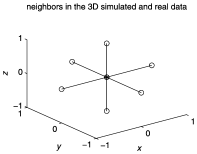

Actual computations indicate that in this example, as long as , is considerably smaller than , indicating that the procedure can adopt a control level much smaller than that of the conventional procedure without excessively encountering the . For example, set ; assume that the neighborhood in the procedure is depicted in the right panel of Figure 1, that is, . Table 2 compares values of and for , . Refer to (38) and (41) in Appendix C for detailed derivations of and , respectively.

The data are generated from a semi-parametric model similar to that in Section 5.2 of Zhang and Yu (2008). (They demonstrated that the semi-parametric model gains more flexibilities than existing parametric models.) The left panel of Figure 6 contains slices (corresponding to the 2D axial view) which highlight two activated brain regions involving activated brain voxels. The neighborhood used in the procedure is illustrated in the right panel of Figure 6.

7 Functional neuroimaging example